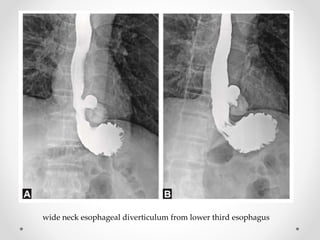

wide neck esophageal diverticulum from lower third esophagus

wide neck esophagealdiverticulum from lower third esophagus